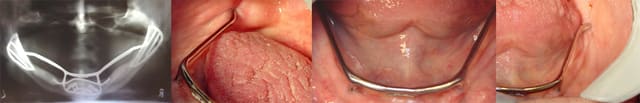

Ceux qui sont encore en bouche marchent très bien. Disons que ceux qui ont eu des problèmes d'exposition ou de déhiscence gingivale ont été déposés !

En voilà un qui a 21 ans.

sauf erreur mon cher Olivier, tu t'es trompé (je savais que je l'aurais) tu nous montre un fort beau cas, sauf erreur de ma part, de sous périosté (j'ai commencé par ça en 84) or je montre un cadre ramique qui est implanté dans la symphise et dans les deux branches ramiques

dessus il etait possible de mettre soit une mobile soit un bridge complet

j'ai un cas posé en 90 (je crois) qui m'a déja "usé" 3 complets

Effectivement mea culpa, il s'agit d'un sous periosté avec appui symphysaire et ramique bilatéral.

Comme quoi, à cette époque, l'implantologie, c'était vraiment du grand art chirurgical !! (sans ironie) Chapeau pxav ! Oser faire des tranchées comme celles là dans les branches montantes, il fallait en avoir des "cojones" !!